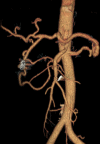

Presentation of case: A 62-year-old man with a two-day history of epigastric pain was admitted at emergency department. CT showed a retroperitoneal haematoma due to a 1.5cm posterior inferior PDA ruptured aneurysm. Angiography had been conducted immediately: both inflow and outflow of the aneurysm were embolized. Another CT scan had been conducted, which revealed residual flow inside the aneurysm sac fed by small collateral vessels. Sub-selective catheterization was repeated and definitive haemostasis was obtained by embolizing the collateral vessels. Postoperative course was uneventful. CT scan follow-up at 36 months showed no abnormalities.

Conclusion: The authors elucidate the importance of occlusion of inflow and outflow of the aneurysm in conjunction with the occlusion of collateral vessels to avert reperfusion of the sac. Simultaneous handling of celiac axis stenosis is still prone to controversy: no relapse of aneurysm have been reported in patients with celiac axis stenosis at long-term follow-up, simultaneous treatment should be reserved when angiography is alarming for likely hepatic or duodenal ischemia.